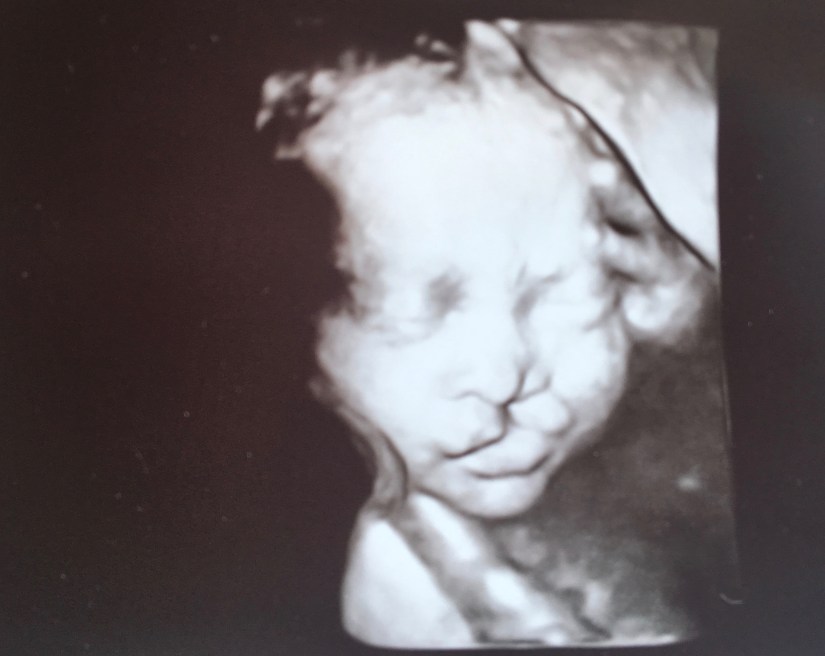

The good news was that baby was growing well. There were no concerns with her size, her heart, her spine, her brain…the clefts were the only things she was dealing with. More good news, the fluid on the kidney resolved. But as always, there’s a bit of bad news too. Some cleft affected pregnancies deal with polyhydramnios. That’s the fancy medical term for excess amniotic fluid. Because of the swallowing concerns that cleft affected babies have, there’s sometimes excess amniotic fluid. This fluid was causing me to measure three weeks ahead, and she was already at a rough estimate of 4 lbs! Possible risks for delivering a baby with “poly” are breech presentation due to the large space babies have to float around in, cord prolapse (where the cord delivers before the baby), and of course premature birth – which I am at risk for anyway due to my history. With this pregnancy, I began doing my own weekly progesterone shots at 17 weeks.